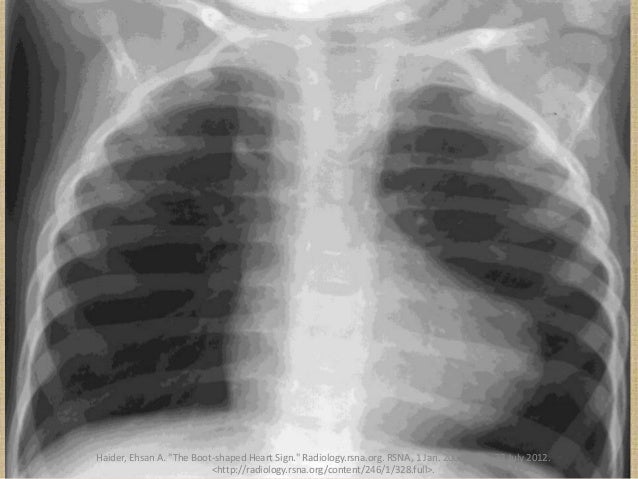

- Boot shape in x-ray(caused by R. ventricle hypertrophy) 靴狀心臟